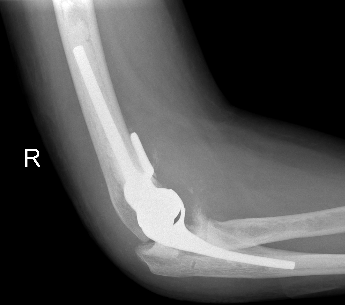

Coonrad-Morrey Discovery Elbow Latitude

Technique Total Elbow Arthroplasty

Vumedi video Coonrad-Morrey approach and prosthesis

Arthroplasty

5. Insert cement restrictors / implant ulna and humeral prosthesis

7. Link components

8. Repair collaterals if needed